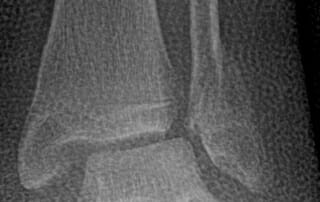

Sprunggelenkverrenkungsbruch – Gelenkspiegelung und offene Operation

Das obere Sprunggelenk ist das am häufigsten verletzte Gelenk. Vor allem beim Sport werden Verletzungen der straffen Bänder – die das Sprunggelenk zu einem funktionsfähigen Gelenk zusammenhalten – auf der [...]